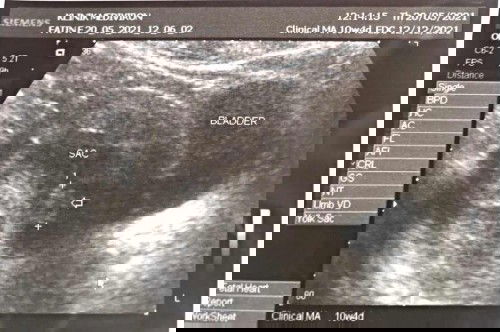

(20/05/2021)Hi Mommies, actually just nak share experience i punya preg scan and doc diagnosed blighted ovum but ending is a good news. Ok first i scan at 6w sbb perut cramp sgt so just nak tau hamil dlm or luar rahim. Result ok dlm rahim and just ada kantung shj. Then 7w i bleeding dkt panties (tak banyak tak sikit). Terus pergi klinik and scan kantung still ada and belum nampak ada isi. Doc remind if esok still bleed terus pergi hosp. But alhamdulillah esok dah tak ada bleeding. Now i dah 10w. i called KK and buka buku 18/05/2021. But nurse check tak dgr heartbeat cs supposedly 10w dah boleh dgr. Nurse bg first appoinment dgn doc 01/06/2021. Tapi i tak puas hati risau why still belum dgr. So the next day 19/05/2021 i pergi swasta scan, lama dia scan sbb nak cari jg baby tu but still tak nampak apa. Time tu nak nangis dah start overthingking balik betul ke i hamil kosong. And i dah start redha if mmg tak ada rezeki. Maybe doc kesian tgk i macam nak nangis so dia scan lg sekali anddd suddenly she saw something. Nampak bayang dalam kantung. Doc ckp tak boleh nak confirmkan sbb tak jelas and tempat dia tak ada mesin utk dgr heartbeat so dia suggest esok i pergi klinik kawan dia dkt mediveron area situ jg utk buat TRANSVAGINAL SCAN. Omg!! I ada baca org cakap tk sakit but still risau if i bleeding lepas buat TVS. Tp sbb nak jg result and jawapan yg dapat puaskan hati ok i agreed buat TVS. Today 20/05/2021 11am i pergi klinik mediveron. Jumpa doc Ros explain itu ini and dia decide kita buat balik scan perut but if still tak nampak apa then we proceed to TVS. I agreed. Time tu miracle happened. Sekejap je doc cari baby and nampak jelas heartbeat baby kelip2 siap ada mesin dgr heartbeat lagi. Happy sgt2 puas lega semua ada dapat tengok and dgr jantung dia laju 😍 husband pun excited dengar hehe. Cuma size baby 8w gitu. Ikut lmp edd 12/12/2021. Ikut scan maybe end sept or 01/01/2022. Alhamdulillah Allah bagi keajaiban utk kami. Sbb sepanjang scan 6w 7w 10w doc dah bg hint hamil kosong. So here i just nak pesan dkt mommies yg experience sama macam i scan awal tak nampak apa, doc ckp itu ini buat kita down, jangan give up always doa fikir yg baik2 and nikmati je moment preggy ni selagi blm ada tanda miscarriege. Jgn stresskan kepala overthingking macam i. Tak elok tau mommies. In shaa Allah semoga dipermudahkan urusan mommies yg lain, enjoy the moment and stay safe! 💗